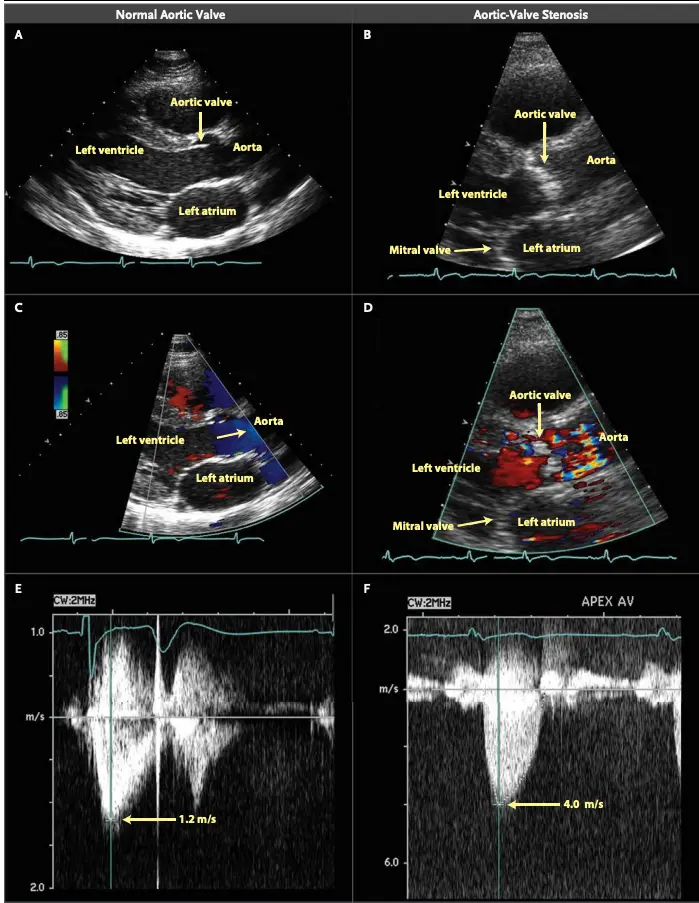

We use the modified Bernoulli equation () to convert the Doppler velocity to pressure gradients across the AV. So as the blood shoots through that tight aortic valve and we clock a velocity of 4 m/s using Doppler on echo, we can convert that to a peak gradient of 64 mmHg, which raises our concern that that poor ventricle is working way too hard.

AVA < 1.0 cm2 Peak velocity > 4 m/s Mean gradient > 40 mmHg Peak gradient > 64 mmHg

Echo for Valvular AS

Board Pearl: If normal Aortic Valve on 2D-echo and high gradient, think subvalvular AS, e.g. Subaortic Stenosis, or supravalvular AS.

- Cannot tell severity of stenosis with 2D-echo alone. You will need Doppler to help determine severity of AS.

- ==Valvular AS will be considered severe if mean gradient > 40 mmHg or peak velocity > 4 m/s (regardless of AVA)==

- Aortic velocity is measured using continuous-wave doppler ultrasound with examination from multiple acoustic windows

- Mean gradient is calculated by averaging instantaneous gradients over the systolic ejection period using the modified Bernoulli equation,

Underestimation due to improper Doppler alignment across the Aortic Valve

If not parallel to the AS jet, you will not get the highest mean AV gradient or peak velocity across the AV → underestimate severity of AS. Importantly, you cannot overestimate the gradient (Exceptions: significant anemia or Subaortic Stenosis).

- The above figure is from the Mayo Echo Boards video where the presenter highlights the importance of calculating the AV TVI in multiple windows to ensure you are appropriately calculating the highest VTI and avoid miscalculation/miscalssification. In Thaden et al (JASE, 2015), the authors found that peak velocity was found outside of the apical window 61% of the time and that neglecting non-apical window misclassified AS 23% of the time.